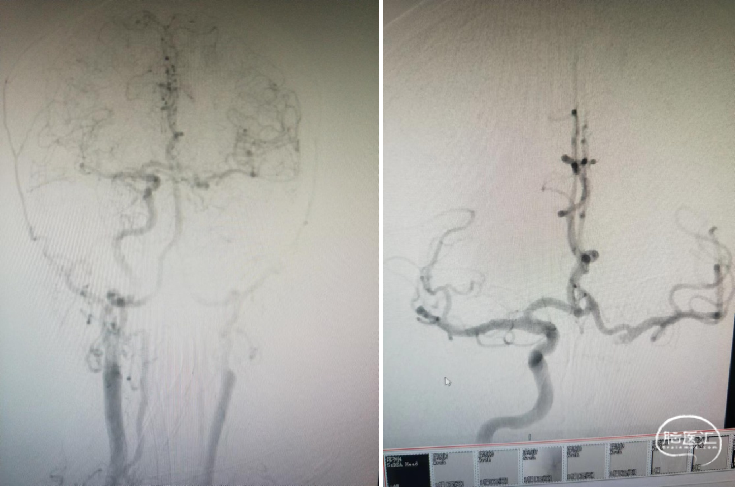

术前DSA

M1闭塞消失 溶栓后血栓移位?M2下干取栓?

手术经过

以8F导引导管做支撑送入右侧颈内C1段,同轴送入132cm-AXS Catalyst-6中间导管、150cm-0.021-Trevo Pro 18微导管、200cm-0.014-Synchro2微导丝;CAT-6送至M1段闭塞处;微导管送入右侧大脑中动脉M2段后,1ml注射器回抽见血液回流再手动造影。

选用4mm×20mm-Trevo Provue取栓支架,将有效段远端放置于大脑后动脉开口处,后退微导管释放支架,见支架尾端存在可疑的释放不全感,提示可能的血栓/狭窄。静待5分钟使支架与血栓镶嵌更紧密。

仅将支架末端无效段拉至CAT-6里面,CAT-6的Y阀处连接50ml注射器负压持续抽吸,同时将中间导管及支架拉出体外,见一35mm×2mm长条血栓附着于支架上,随后20ml注射器于长鞘内再次抽吸,可见顺畅血流进入注射器。

复查造影:下干完全再通。

静待15分钟后再次复查造影,见患者血管通畅,前向血流良好,mTICI 3级。大脑前动脉、前交通动脉血流通畅,对侧M1显影良好,术中患者生命体征平稳,术毕。